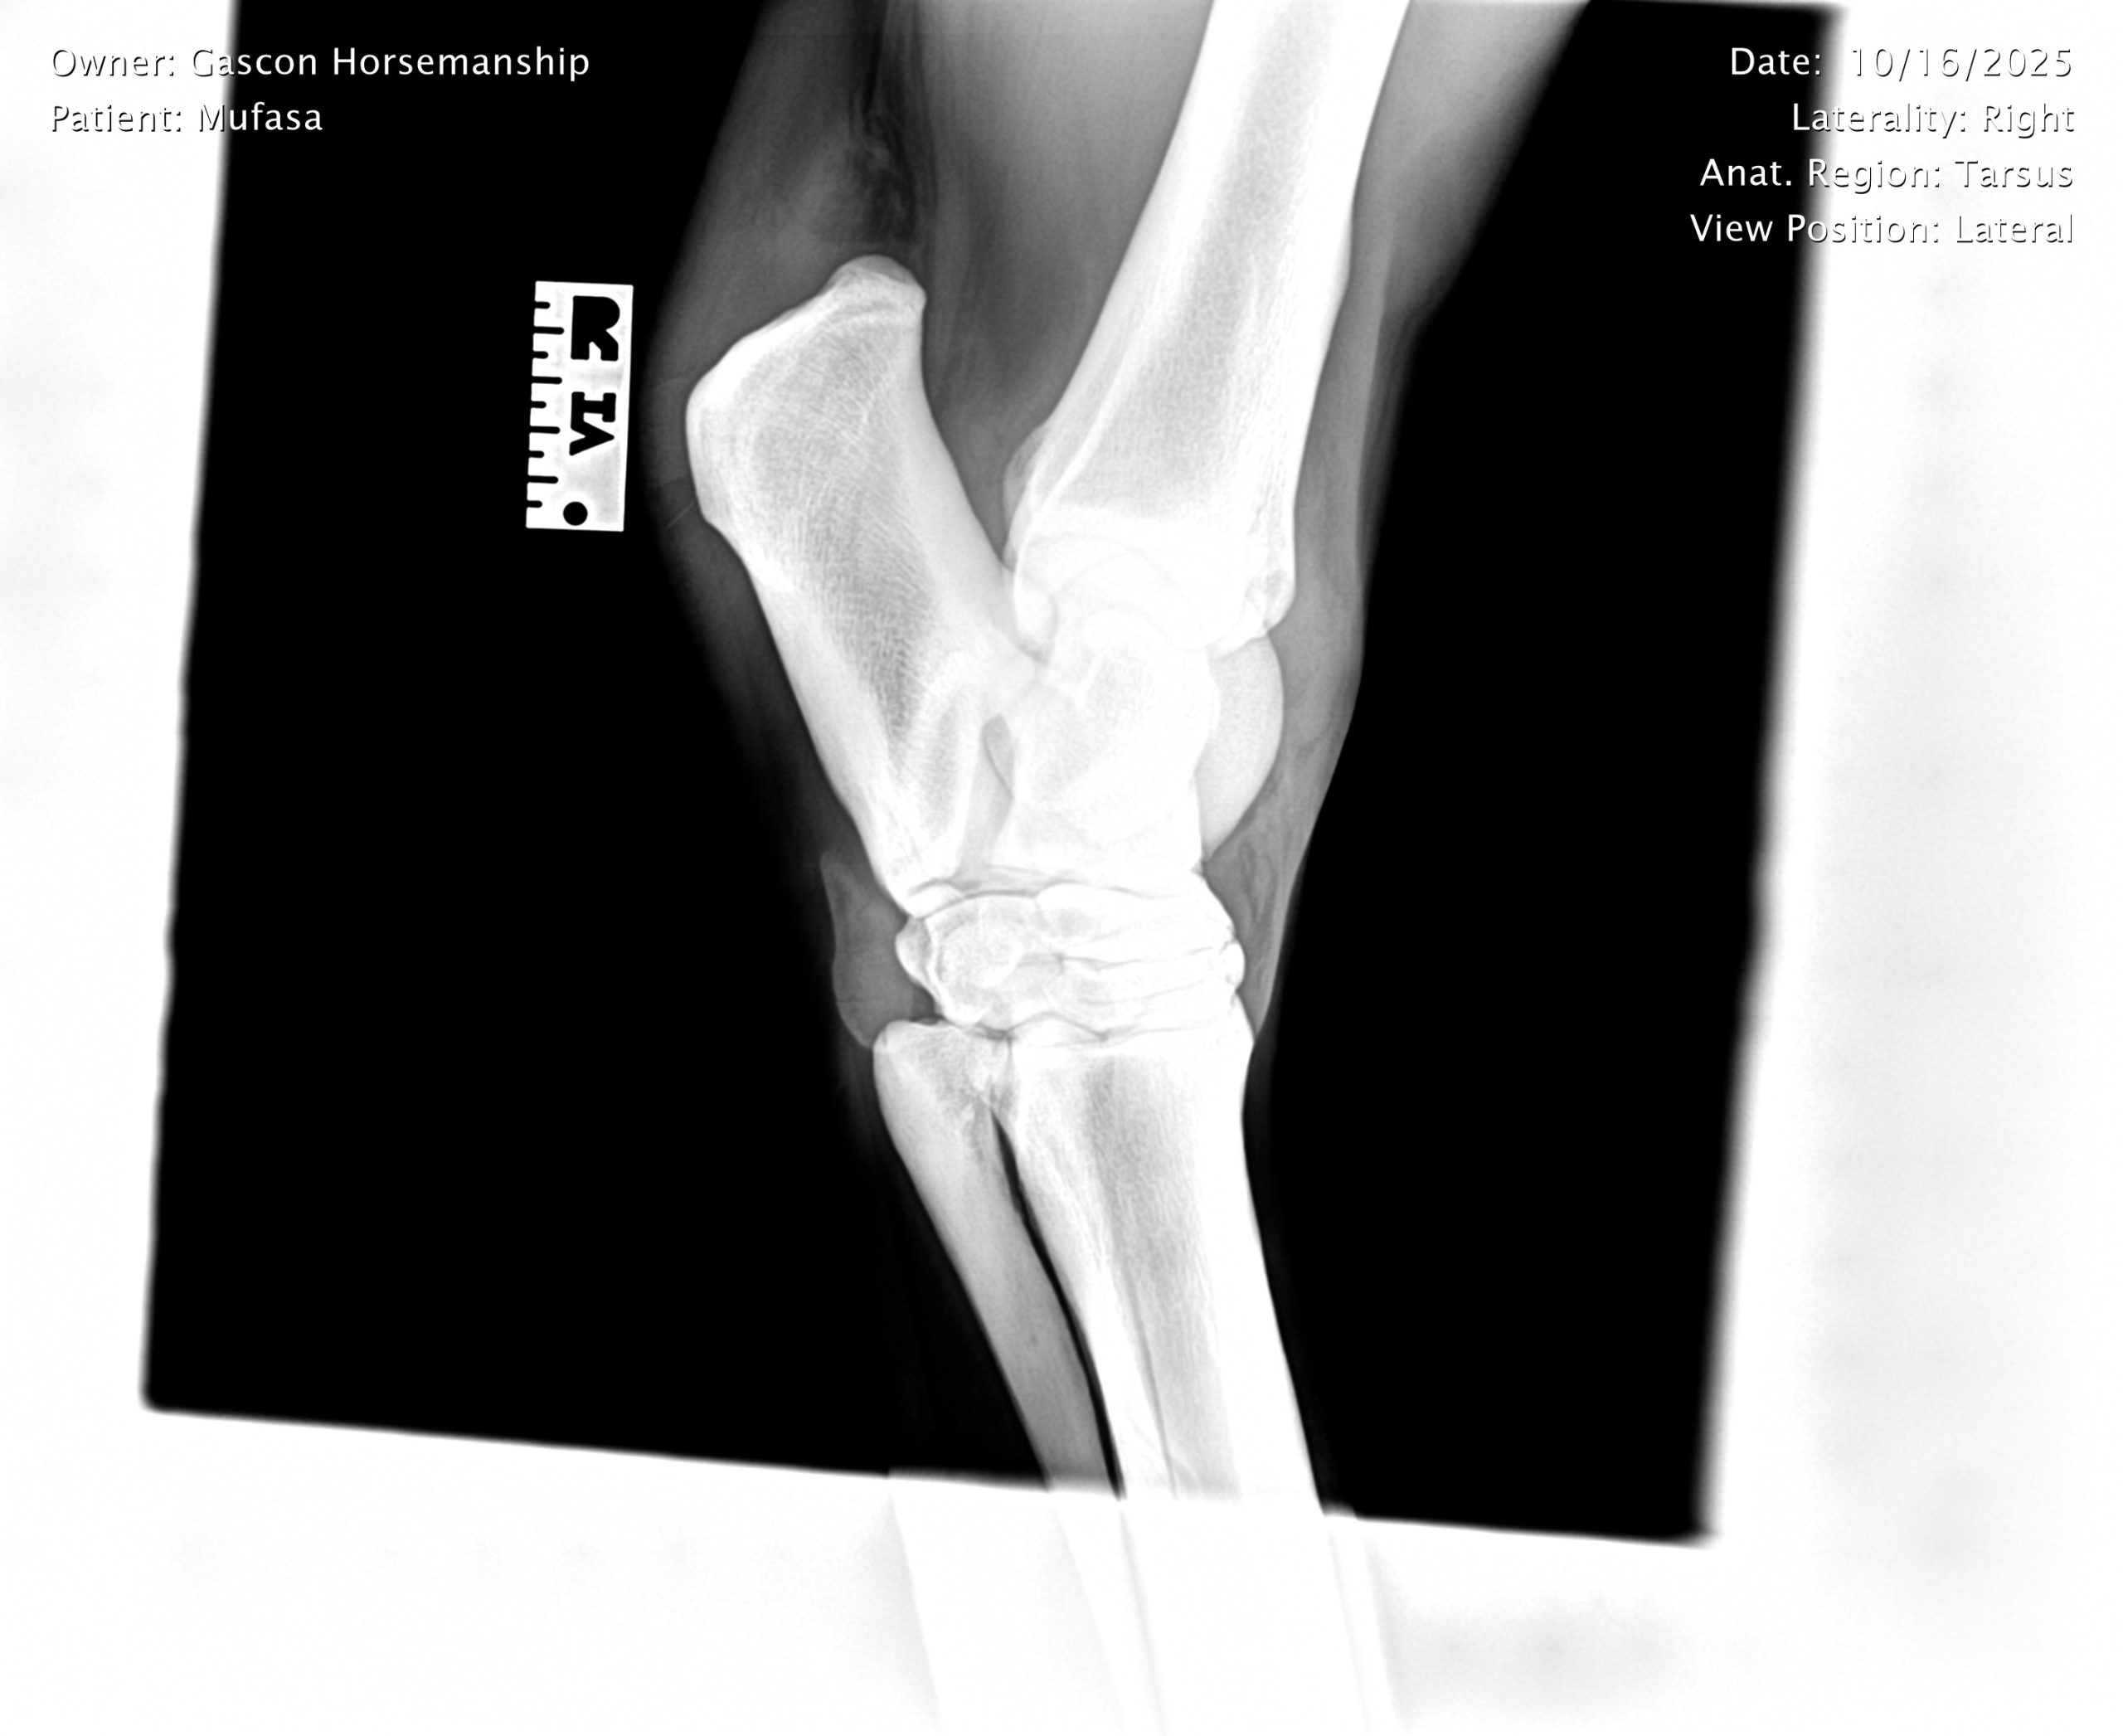

He already has a full pre-purchase exam on file, complete with 25 X-rays included in his album.